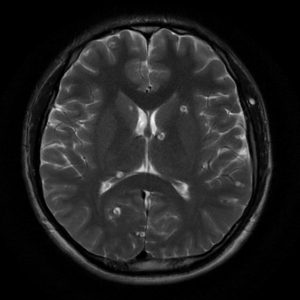

Di căn não

Lượt xem: 216» 19-06-2020 -